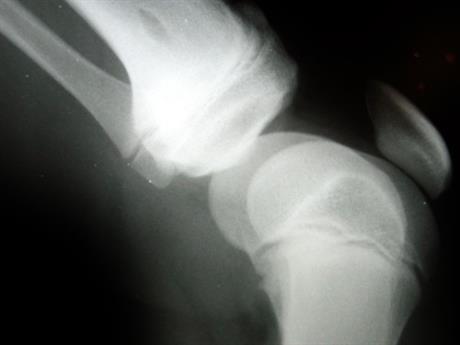

Oporavak nakon artroskopije koljena

Iako poštedna, artroskopija je ipak operacija, te po njoj valja doslovno slijediti upute liječnika i fizioterapeuta kako bi se izbjegle moguće komplikacije